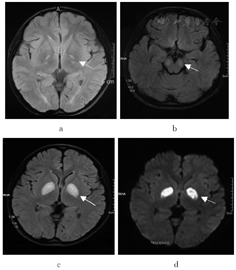

入院后即行实验室检查、电生理检查、影像学检查等,并对患儿及家族成员线粒体病相关核基因突变情况进行检测分析。结果显示:患儿血清C反应蛋白144.5 mg/L,血沉36 mm/h,降钙素原定量0.57 μg/L,静息血乳酸波动在3.6~5.6 mmol/L,均增高。心电图、脑电图未见特异性改变;肌电图提示四肢多发周围神经病变;四肢体感诱发电位显示深感觉传导通路轻度异常;胸部CT提示双肺炎症。患儿2a前于外院头颅MRI显示双侧苍白球对称性条状长T1长T2信号,FLAIR、DWI高信号;本次入院头颅MRI显示双侧大脑脚、豆状核对称性片状长T1长T2信号影,FLAIR、DWI高信号影(图1)。基因检测发现,患儿PDHA1基因存在半合子突变,c.376 C > T (p. Arg126Cys)。患儿母亲存在PDHA1基因该位点的杂合突变,其父亲、弟弟、姨、舅舅均未发现该基因突变。该变异符合X连锁遗传方式,其母为变异携带者。

注:a为2a前头颅MRI影像,示双侧苍白球对称性FLAIR序列高信号;b-d为本次就诊时头颅MRI影像,b显示双侧大脑脚对称性FLAIR序列高信号,c-d显示双侧基底节区豆状核对称性FLAIR和DWI序列高信号。